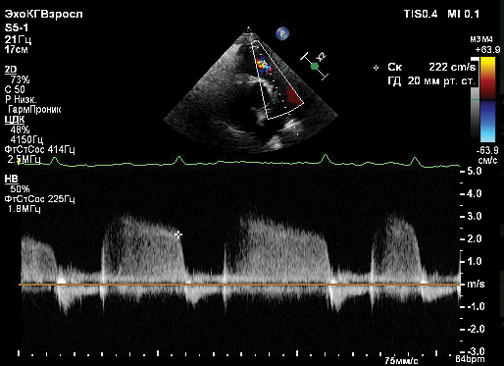

Структура миокарда желудочков также различается. Свободная стенка ПЖ представлена в основном поперечными волокнами и небольшой долей субэндокардиальных продольных волокон. В ЛЖ эндокардиальные и эпикардиальные волокна формируют спиральную структуру, дополненную циркулярными волокнами в среднем слое. Следовательно, миокард ПЖ тоньше по сравнению с миокардом ЛЖ (примерно одна треть ЛЖ) [6]. Наряду с различиями в анатомии, ПЖ имеет более высокое содержание внеклеточного матрикса по сравнению с ЛЖ [10], что делает его более комплаентным к возврату венозной крови без существенного повышения конечного диастолического давления к норме. ПЖ имеет серповидную форму, тогда как ЛЖ — конусообразную. ПЖ разделен на три сегмента: приносящий отдел, включающий трикуспидальный клапан, хорды и папиллярные мышцы; верхушка; выносящий отдел (конус или инфундибулум). ПЖ сокращается перистальтической волной от синуса к конусу [11]. Поверхностный слой миокардиальных волокон ПЖ связан с волокнами ЛЖ, что объясняет движение свободной стенки ПЖ в сторону межжелудочковой перегородки во время систолы. Более глубокий слой вертикально ориентированных волокон обеспечивает продольное укорочение ПЖ, что используется в эхокардиографии (ЭхоКГ) для оценки функции ПЖ с помощью измерения амплитуды систолического движения кольца трикуспидального клапана (tricuspid annular plane systolic excursion, TAPSE). TAPSE <18 мм ассоциировано с неблагоприятным прогнозом у пациентов с ЛАГ. Комбинированный параметр TAPSE/систолическое давление в легочной артерии (СДЛА) (норма >0,55 мм/мм рт.ст.) тесно связан с сопряжением ПЖ и легочной артерии (ПЖ-ЛА) и прогнозирует исход заболевания [12]. Tello K, et al. (2018) проанализировали клиническую значимость соотношения TAPSE/СДЛА у 290 пациентов с ЛАГ [13]. Соотношение TAPSE/СДЛА <0,19 мм/мм рт.ст. было ассоциировано с более худшими показателями гемодинамики и физической работоспособности по сравнению с пациентами, имевшими более высокий показатель TAPSE/СДЛА (0,19-0,32 мм/мм рт.ст. и >0,32 мм рт.ст., соответственно). Учитывая тесную взаимосвязь показателя сопряжения ПЖ-ЛА с выживаемостью пациентов с ЛАГ, клиническими и гемодинамическими показателями, соотношение TAPSE/СДЛА было внесено в шкалу стратификации риска летальности ESC/ERS2022 в качестве одного из предикторов летальности [1]. Другим показателем систолической функции ПЖ является скорость движения латеральной части фиброзного кольца трикуспидального клапана (TAPSV или S’, см/с), который определяется с помощью тканевой допплерографии. Значение S′ >10,5 см/сек ассоциировано с сохранной систолической функцией ПЖ [14].

Рис. 2. Примеры ПЭТ/КТ изображений с [ 18F]-ФДГ: (А) пациент без ЛГ (контрольная группа); (Б) пациент с ЛАГ.

Примечание: визуализируется повышенное накопление радиофармпрепарата [ 18F]-ФДГ в миокарде правого желудочка при ЛАГ (красная стрелка) по сравнению с миокардом ПЖ у пациента без ЛГ (желтая стрелка) (собственные данные).

Рис. 3. Накопление [ 18F]-ФДГ миокардом ПЖ в зависимости от категории риска летальности ESC/ERS 2022 у пациентов с ИЛАГ (верхний ряд — МРТ пациентов с ИЛАГ в зависимости от категории риска летальности; средний ряд — ПЭТ/КТ с [ 18F]-ФДГ; нижний ряд — показатели КПКС в соответствии с категорией риска летальности) [42].

Сокращения: ЛСС — легочное сосудистое сопротивление, среднее ДЛА — среднее давление в легочной артерии.